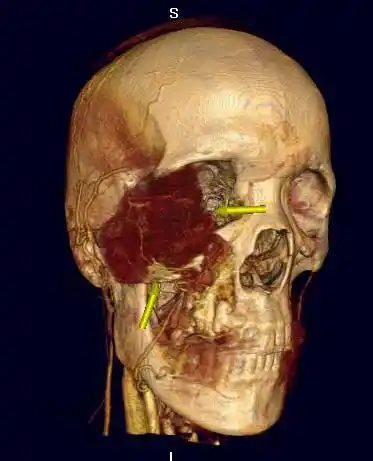

典型右侧上颌窦癌1例